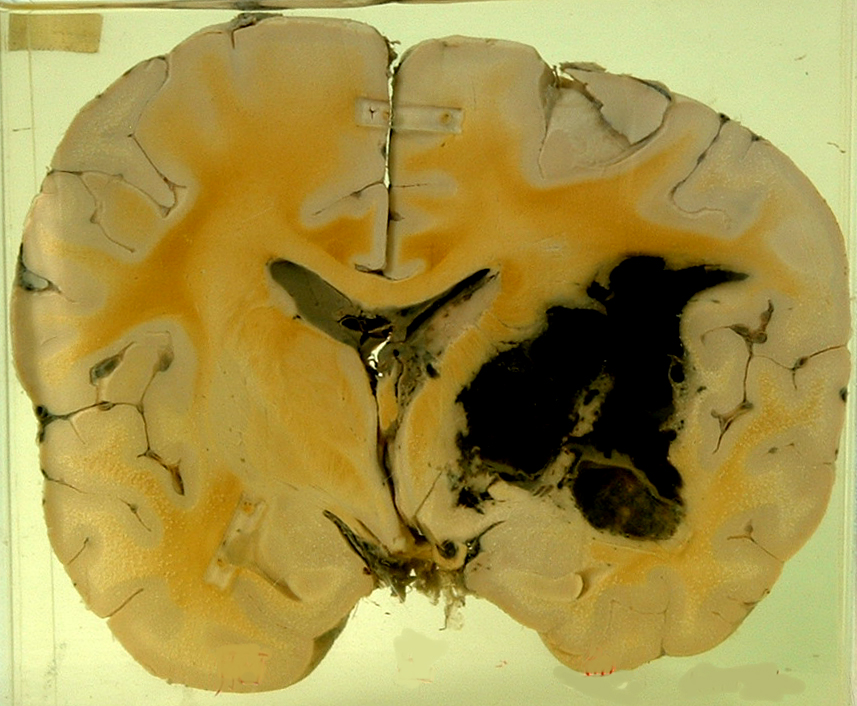

3.脑出血